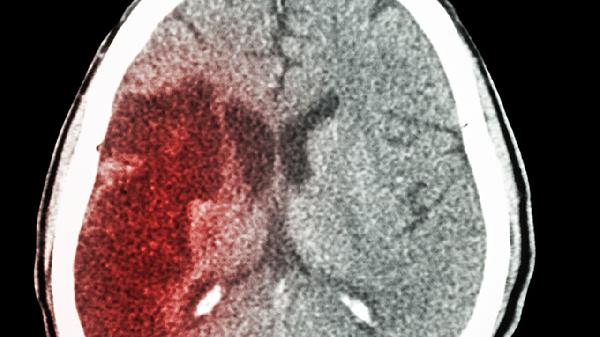

婴幼儿脑出血后遗症具体有哪些表现

婴幼儿脑出血后遗症主要表现为运动功能障碍、认知发展滞后、语言沟通困难、癫痫发作以及视觉和听觉方面的异常。这些后遗症的发生与出血的位置、出血量及治疗的及时性密切相关,因此早期进行康复干预对于改善预后非常重要。